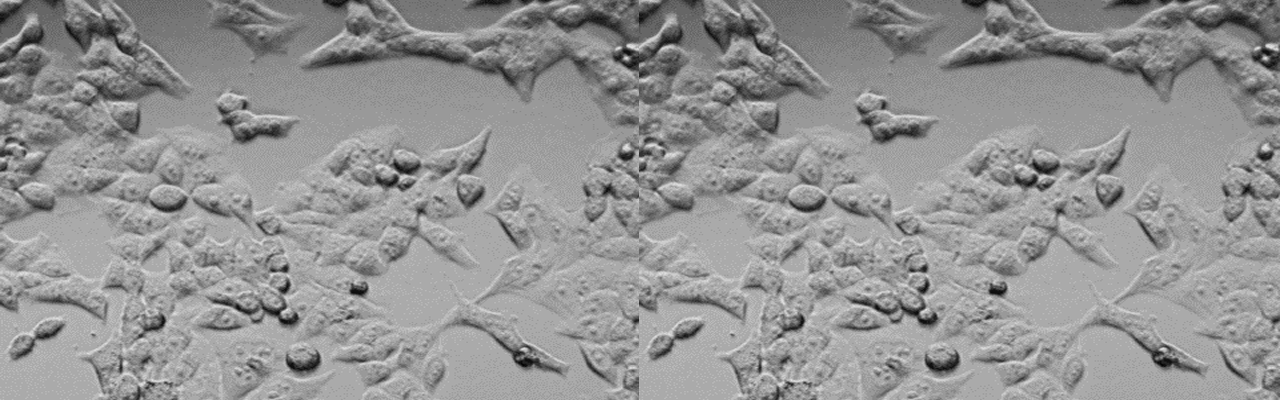

| 细胞全名 | 人脑神经母细胞瘤细胞 |

| 生长特性: | 偶尔上皮细胞空泡 |